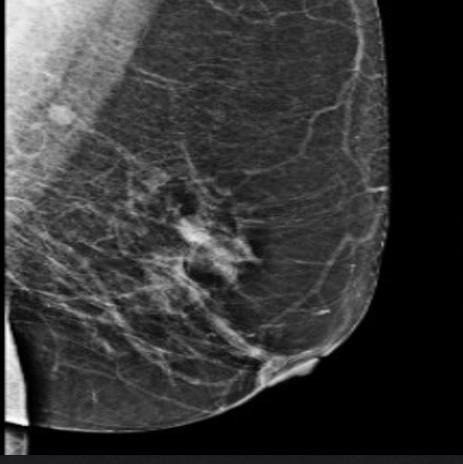

Eldiagnósticoporimágenesenoncologíaes esencial,yaquepermiteladetecciónprecoz, mostrandolesionesprecancerosasantesde quesevuelvanmalignas,olesionestumorales enpacientesasintomáticos;ayudaaidentifi‐carelorigendeltumor(órganoprimarioafec‐tado),susefectosenlasestructurasadyacen‐tes(metástasis);sepuedeestablecerunalis‐tapriorizadadediagnósticosdiferencialesy posteriormenteundiagnósticodefinitivo mediantebiopsias(extraccióndeunpequeño fragmentodetejido)guiadasporalgúnméto‐dodeimagenparaenvíoacitologíaehisto‐patologíaparadescartaroconfirmarcáncer; estableceunaestadificación:sabersihay cáncerenetapasiniciales(aestoselepuede llamardeteccióntemprana)oenetapas avanzadas.Estainformaciónesvaliosapara quesepuedaelegireltratamientoadecuado (cirugía,radioterapia,quimioterapiaocombi‐nacióndeestasmodalidades);Ayudaenla valoracióndelarespuestaaltratamiento.

Lasprimerastécnicasdediagnósticoporima‐genqueseutilizaronfueron,enprimerlugar,la radiografíayposteriormentelaecografía, ambascaracterizadastantoporsudisponibili‐dadcomoporsurentabilidadyquealdíade hoysesiguenutilizandoypodríanconsiderar‐sedeprimercontacto.Enlaactualidad,latec‐nologíamédicamodernatieneunagranvarie‐daddemétodosdediagnósticoporimágenes comolatomografíacomputarizada(TC),la imagenporresonanciamagnética(IRM),la mastografíaytomosíntesis(estosdosúltimos

Estudiodemastografíademamaizquierdademujerasintomática,queacudeaestudiodedeteccióndecáncerde mama,enproyecciónoblicuamediolateral(a),cefalocaudal(b)dondeseidentificaunnóduloirregularencuadrante superiorexterno,queenconodecompresión(c)elnódulopresentaespículas,porloquesecategorizacomoBIRADS5.

sonmétodosqueseutilizanespecíficamente paradetectarelcáncerdemama).